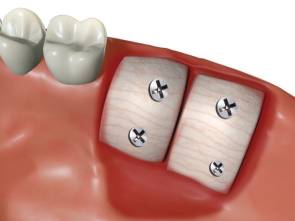

歯を失うと骨の吸収が進行し、理想的な位置にインプラントを埋入すると骨が不足します。

切り出してきた骨を不足する部位にチタンスクリューで固定します。

骨の成熟を待って、インプラントを理想的なポジションに埋入します。